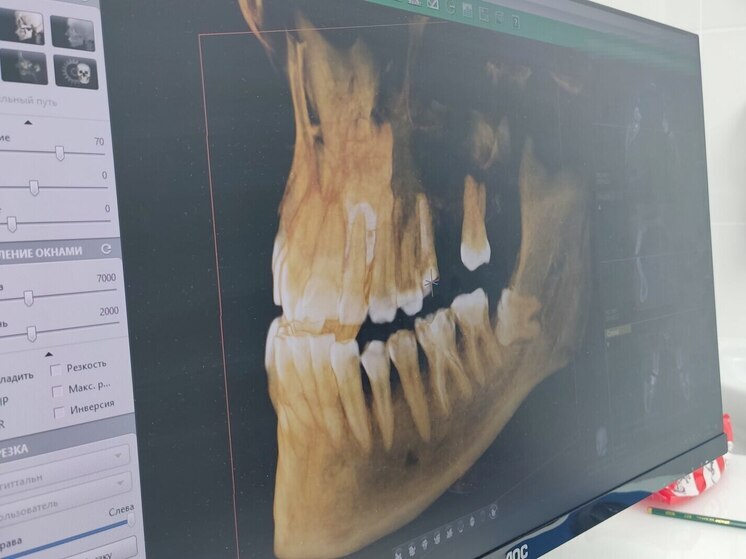

Состояние вашей улыбки тесно связано не только с зубами, но и с осанкой, положением челюсти и здоровьем позвоночника. Об этом рассказали специалисты Киришской стоматологической поликлиники.

Специалисты подчеркивают, что голова – это единая система: если есть проблемы, то это влияет и на челюстной сустав, а также шею и спину. В таких случаях на помощь приходит остеопат, который может значительно улучшить результаты стоматологического лечения:

Если у вас нарушения прикуса или привычка напрягать шею, специалист помогает сбалансировать кости черепа и расслабить мышцы. Это создает оптимальные условия для установки брекетов или протезов.

Такое лечение полезно для людей с брекетами, тех, кто готовится к протезированию или имплантации, страдает от скрежета зубами, а также при необъяснимых головных болях или щелчках в челюсти.